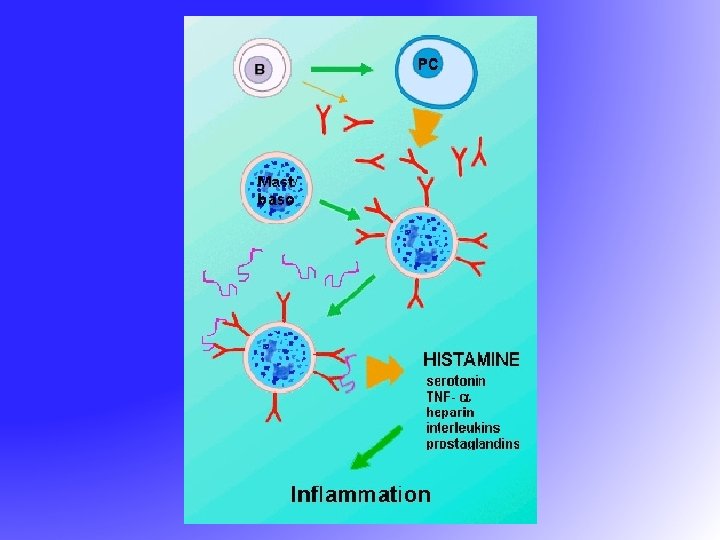

Allergic Rhinitis and its Impact on Asthma (ARIA) • 30% of patients with AR have asthma • The majority of patients with asthma have AR • AR is a major risk factor for poor asthma control • All patients with AR should be assessed for asthma

Allergic Rhinitis and its Impact on Asthma (ARIA) • 30% of patients with AR have asthma • The majority of patients with asthma have AR • AR is a major risk factor for poor asthma control • All patients with AR should be assessed for asthma

Allergic Rhinitis - Causes Seasonal (Intermittent) • Pollen from ü Grasses ü Weeds ü Trees • • • Perennial (Persistent) House dust mites Mold and fungus spores Cockroaches Animal dander Food Chemicals

Allergic Rhinitis - Causes Seasonal (Intermittent) • Pollen from ü Grasses ü Weeds ü Trees • • • Perennial (Persistent) House dust mites Mold and fungus spores Cockroaches Animal dander Food Chemicals